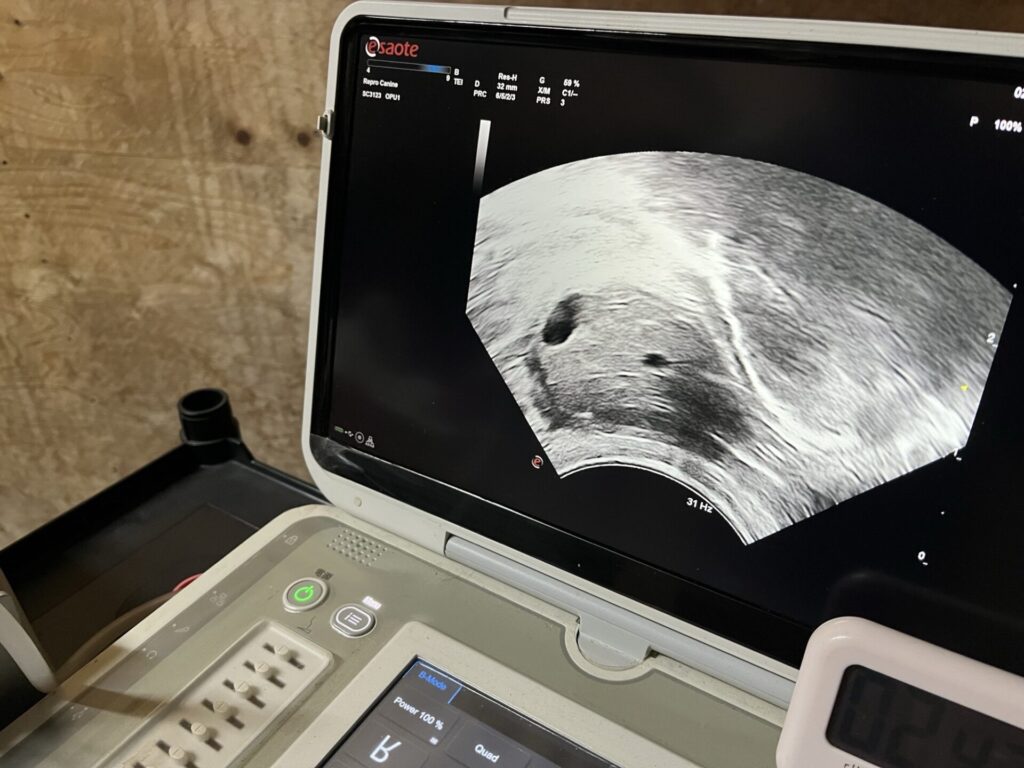

2月のOPU結果が出たのでご報告します。

OPUの利点として、間隔を空けることなく、連続して採卵が可能という点があります。

今回の4頭は1月の4頭と一部同じ個体で実施しました。

間隔としては6週間です。

また、①と④は10日ほど前にAIをしており、このように、妊娠牛からも採卵できるのがOPU最大の強みです。

2週間間隔で出来るという報告もありますが、うちでは、そこまで間隔を詰めると少し生産率が落ちるという感触があります。

それにしても、母体が授精中でありながら、6週間(2回の採卵)で、①は17+5=22個、④は12+20=32個もの受精卵が得られるとは!

しかしこれもやはり個体差があり、採れる卵子自体が少なかったり、質があまり良くなかったりということがあります。